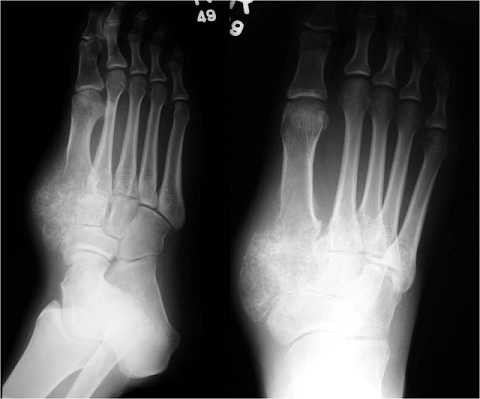

Ung thư xương cẳng chân

Đây là dạng ung thư xương phổ biến ở nam giới, thường xuất hiện ở độ tuổi dậy thì. Nam giới có nguy cơ u xương cẳng chân ác tính cao gấp 2 lần so với nữ giới và thường gặp ở những người có chiều cao vượt trung bình.

Những triệu chứng ung thư xương cẳng chân phổ biến nhất chính là tình trạng sưng, đau ở cẳng chân, đôi khi có thể nhìn rõ khối u bướu. Một số bệnh nhân thường đau nhiều vào ban đêm hoặc khi tập thể dục.

U xương ác tính cũng thường phân bố ở xung quanh khu vực đầu gối. Và trong một số trường hợp hiếm gặp thì ung thư xương cẳng chân có thể di căn từ xương tới các dây thần kinh hay mạch máu ở các chi.